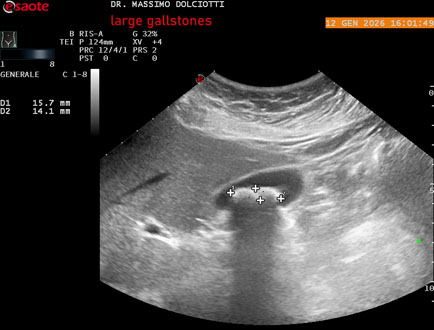

Data inserimento: 14/10/2020

Ecografia del: 28/09/2020

Strumento: Esaote MyLab Twice

Sonda: Convex Multifrequenza 1-8 MHz

Età Paziente: F 47 anni

Motivazione dell'esame: follow up di litiasi della colecisti.

Commento all'esame: le immagini ed il video documentano immagini iperecogene, con cono d'ombra posteriore nel lume della colecisti, delle dimensioni di 18,9 mm e 14,2 mm, da ricondurre a 2 grandi calcoli della colecisti.

Conclusioni: 2 grandi calcoli della colecisti (2 large gallstones).

Presentazione: Dr. Massimo Dolciotti - Ancona

Elaborazione digitale: Andrea Dini - Ancona